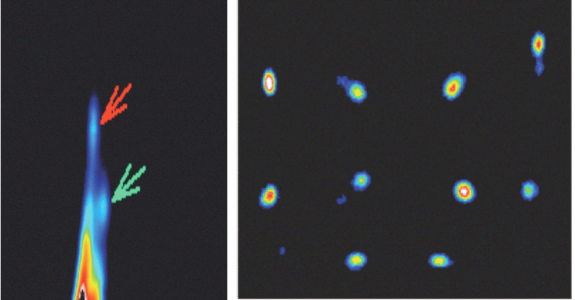

| ABSTRACT | Introduction: Simultaneous in-vivo imaging of several biological processes may improve oncological, neurological and cardiovascular studies by providing complementary information obtained under the same exact conditions and coregistered in space and time. Standard PET imaging does not allow multiplexed acquisitions, as all annihilation photons have the same energy. We developed a technique called multiplexed PET (mPET), which uses a tracer labelled with a pure positron emitter (such as 18 F, 13 N, 11 C), and a tracer labeled with a positrongamma emitter (such as 124 I, 76 Br, 82 Rb, 86 Y). Positrongamma emitters generate a significant number of triplecoincidences , which allows them to be differentiated from the standard PET radionuclides . In this work, we evaluated the performance of mPET using phantom and animal experiments. |

| ABSTRACT | When multiple pinholes are used to acquire SPECT projection data, there may be regions on the detectors where data from two or more pinholes overlap. Such “multiplexing” of projection data can cause artifacts and/or increased noise in reconstructed SPECT images, depending on the exact acquisition geometry. We previously described a modified MLEM algorithm that alternates between (i) estimating the separated projection data that would be obtained through each individual pinhole (i.e., demultiplexed data), based on the current MLEM iteration’s image, and (ii) reconstructing the SPECT image by MLEM, but assuming that the demultiplexed data estimates are the actual measured data. The modified MLEM algorithm was first tested with data simulated for a stationary 39pinhole collimator tube, and more recently with Tc99m phantom data acquired from three vials of different sizes on a 6pinhole, tripledetector SPECT camera. |

| ABSTRACT | Positron emission tomography (PET) is one of the most sensitive noninvasive molecular imaging tool, being its sensitivity several orders of magnitude higher than that typically obtained in single photon emission computed tomography (SPECT). However, PET lacks the ability of SPECT to multiplex signals from several tracers, which is very useful in many different studies such as cardiac imaging with 99mTcSestamibi and 201Tl. Recently, it has been shown that the use of tracers labelled with positrongamma emitter radionuclides like (124I, 86Y, 82Rb, 94mTc, 76Br) in combination with tracers labelled with standard positronemitter radionuclides like (18F, 11C, 13N) enables multiplexed PET (mPET). mPET uses the triple coincidences from the positrongamma emitters, together with the standard double coincidences to reconstruct separated images of each radionuclide’s activity distribution. We obtained encouraging results with mPET in some initial preclinical studies, but a detailed study of the quality and quantification properties of mPET images, and an evaluation of its performance in realistic clinical scenarios was still required. |

| ABSTRACT | Nonstandard PET radionuclides like 124 I, 76 Br, or 86 Y, emit prompt gamma rays together with the positrons which can be detected in coincidence with annihilation photons, creating spurious double coincidences. This causes a background in the PET images that reduces contrast and hampers quantitative accuracy. Existing correction methods are computationally intensive and since they depend on the size of the subject and on the accuracy of a number of complicated estimates, they may be valid for large source distributions only up to a certain size. To overcome these challenges, we have implemented a novel correction which is based on the measurement of positron+gamma triple coincidences. |